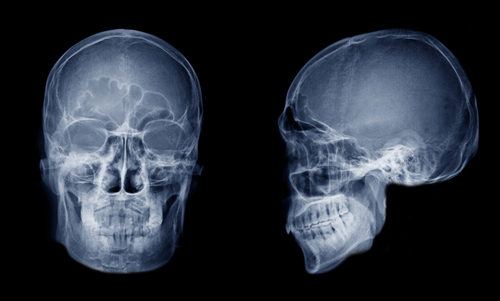

Как делается рентген пазух носа

Пациент приходит к назначенному времени, врач разъясняет, что показывает рентген носовых пазух и как проходит процедура. В кабинете рентген-лаборант помогает занять нужную позу, закрывает щитовидную железу и грудь защитным фартуком, кратко объясняет, куда смотреть и как дышать. Рентгеновский аппарат выполняет экспозицию, и изображение сразу видно на экране. Выбор проекций зависит от клинической задачи и предполагаемого заболевания — именно они определяют, что будет лучше видно.

- Обзорная прямая. Универсальный старт: видно носовую полость, симметрию синусов, велик ли объем «затемнения». Такой формат рентгена пазух носа подходит для экспресс-оценки и контроля после лечения.

- Боковая. Помогает оценить верхнезадние отделы, хоаны, соотношение структур носоглотки. Подразумевает рентген носовых пазух в боковой проекции, когда врачу важен «профиль» анатомии.